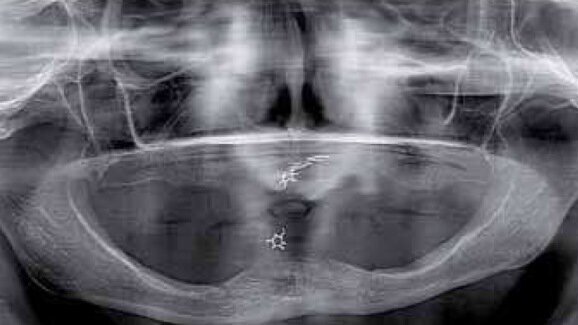

W fazie planowania leczenia wykonano badania OPG oraz CBCT. Badania uwidoczniły masywny zanik części zębodołowej wyrostka żuchwy do jej trzonu – klasa 3. Zanik ten nie wykluczał leczenia pacjentki, jednak eliminował żuchwę jako miejsce dawcze dla ewentualnych przeszczepów kości dla rehabilitacji szczeki. W szczęce uwidoczniono masywny zanik części zębodołowej wyrostka w odcinku przednim wraz ze zwiększeniem upowietrznienia zatok szczękowych i deformacją płaszczyzny powierzchni kości. Jest to obraz typowy dla pacjentów użytkujących przez lata protezy całkowite w szczęce przy współistniejącym uzębieniu resztkowym w odcinku międzybródkowym żuchwy. Taki stan nazywamy zespołem Kellego (Ryc. 1).

Taki stan jest ogromnym utrudnieniem dla leczenia protetycznego bezzębnej szczeki przez niekorzystną relację płaszczyzny pola podparcia protezy do płaszczyzny protetycznej. Znaczny stopień zaniku wyrostka w okolicy podnosowej eliminuje to miejsce z zabiegów GBR. Do rozważań pozostają zatem odcinki boczne w rzucie zatok szczękowych. W przypadku opisywanej pacjentki CBCT uwidoczniło zadowalający wymiar wertykalny przy ubytku horyzontalnym w postaci bagnetowatego szczytu wyrostka zębodołowego (Ryc. 2).